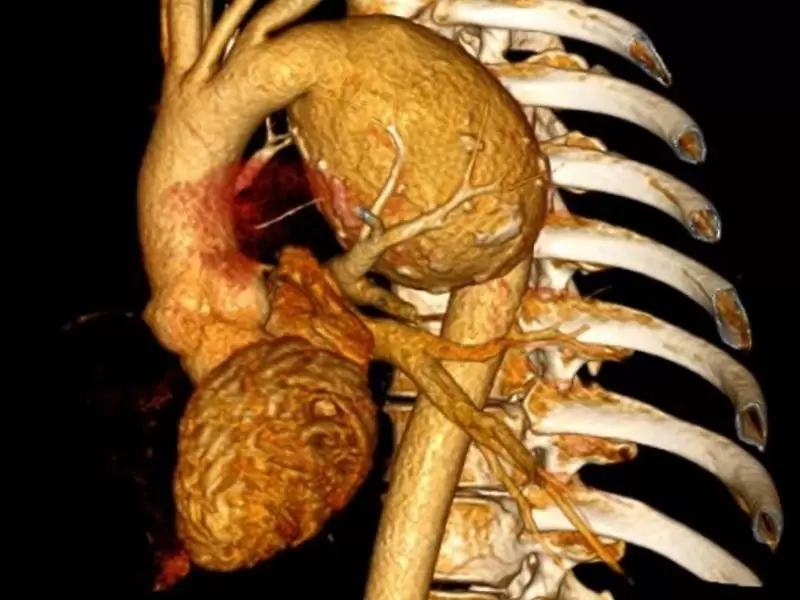

Sağlık Bakanlığı kalite yönetimine göre A Sınıfı (bölgenin en büyük kardiyoloji ve kalp damar cerrahisi) dal hastanesi olarak hizmet vermektedir. 40 standart oda, 2 engelli odası, 8 yatak üçüncü basamak Yoğun Bakım Ünitesi ,laminer floor sistemli 60’ar metrekare büyüklüğünde 3 ameliyathane salonu ve steril depo ,anjio salonu, röntgen, tomografi salonu bulunmaktadır.

Sağlık Bakanlığı kalite yönetimine göre A Sınıfı (bölgenin en büyük kardiyoloji ve kalp damar cerrahisi) dal hastanesinde tedavi olun.